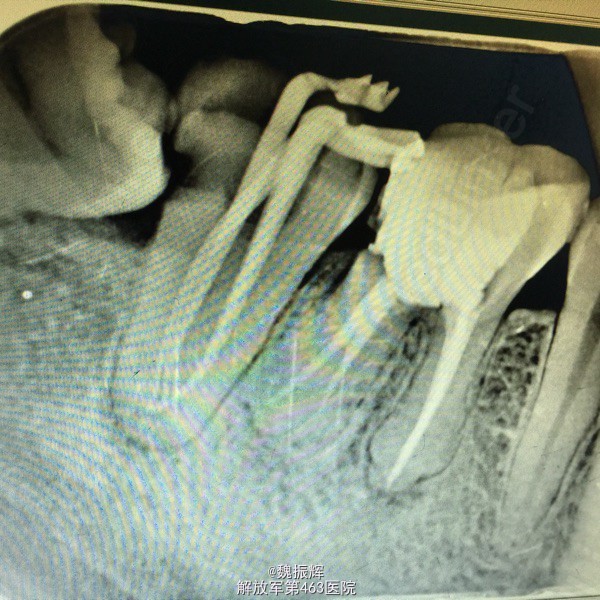

患者毕某,女性,右下后牙不适数日。数日来右下后牙自发痛影响睡眠,影响进食,来院就诊。

查体:47远中邻面龋坏,探(+),冷(+),叩(-),X线示远中龋坏近髓,48近中阻生,47,48之间食物嵌塞。

诊断:牙髓炎 处理:局麻下,47降牙合,去腐,开髓,揭髓顶冲洗,拔髓,根管疏通测量及机用镍钛器械进行根管预备,次氯酸钠进行根管冲洗,大椎度牙胶尖试尖,进行根管充填。Zoe暂封,观察嵌体修复。择期拔除48。

对于无咬合的阻生齿应该尽早拔除以免对其他牙齿造成损害。